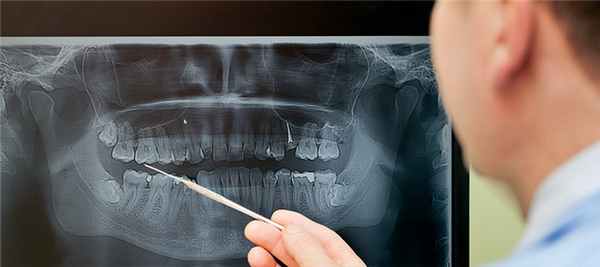

Современный рентген зуба: визиограф и его преимущества

Для проведения рентгена зубов максимально быстрым и качественным способом, стоматологи нашей клиники используют современный аппарат визиограф. С его помощью изображение в реальном времени выводится на монитор компьютера, что позволяет получить качественную и актуальную картину состояния зубной поверхности, как на наружной, так и на внутренней стороне. При этом данный метод рентгена зубов имеет следующие важные преимущества:

- Моментальное получение изображения.

- Снижение лучевой нагрузки на врача и пациента практически в 10 раз.

- Более высокое качество готовых изображений по сравнению с классическим использование рентгеновской пленки.

- Доступ к измерению глубины зубного канала.

Такой рентген, применяемый в современной стоматологии, позволяет сделать самую глубокую диагностику, что в значительной степени повышает качество последующего лечения.

Рентген зубов

«Кремлёвская стоматология» оснащена совершенным рентгенодиагностическим решением для любой первоклассной клиники – аппаратом ORTHOPHOS SL 3D Ceph. Это универсальный рентгеновский аппарат, который облегчает диагностику и обеспечивает идеальные результаты: начиная с невероятно резких и контрастных панорамных 2D снимков, получаемых с помощью датчика прямого преобразования DCS и технологии резкого слоя SL, и заканчивая высокоточными 3D-изображениями благодаря настраиваемому полю обзора и более простому и безопасному позиционированию пациента.

Совместная работа ORTHOPHOS SL 3D с программным обеспечением SIDEXIS 4 открывает еще больше возможностей для решения стоматологических задач, позволяя клинике работать еще более эффективно.

Для быстрой и безопасной интраоральной рентгенографии «Кремлёвская стоматология» обладает системой HELIODENTPLUS – это интраоральная рентгенографическая система новейшего поколения, ориентированная на потребности специалистов. Она долговечна и безопасна.